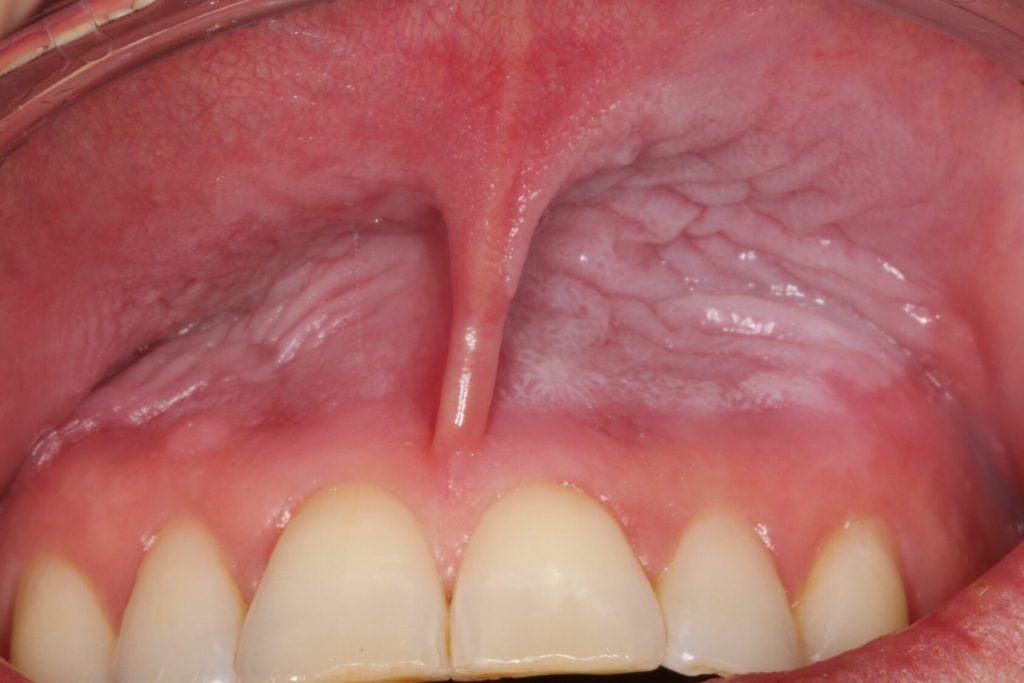

A new study has been initiated at the University of Gothenburg to study the effects on oral health from using nicotine pouches. The university has released a statement detailing that the study is being initiated because a number of dental patients referrals from dental clinics to the University. These patients have gum damage that differs from what is commonly seen in users of traditional tobacco-based snus. This statement has been widely reported by Swedish news media.

A pilot study with 23 Swedish dentists who were daily pouch users of either tobacco snus or nicotine pouches (referred to as “white snus” in the University of Gothenburg statement , several of which had similar gum issues to those documented by Dr Gale including irritated or inflamed gums, snus lesions and receding gums. In our test the occurrence and severity of gum irritation and snus lesions was reduced significantly when users switched to using only Stingfree pouches for 5 weeks. Stingfree pouches have the same type of contents as ordinary pouches but the pouch itself has a protective layer called PROTEX that prevents direct contact between the pouch contents and the users’ gums.